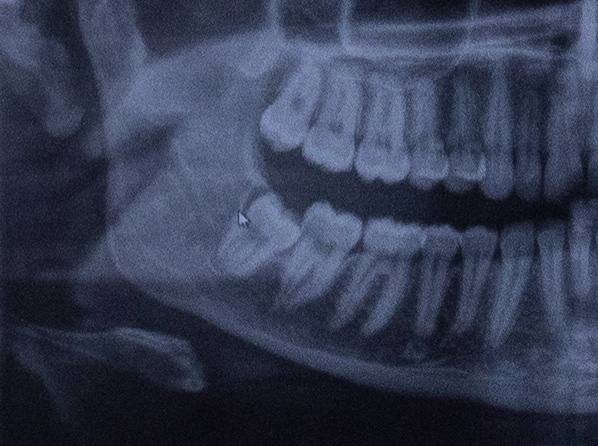

LÖWENZAHN documents the removal of a young woman's wisdom teeth over two days.